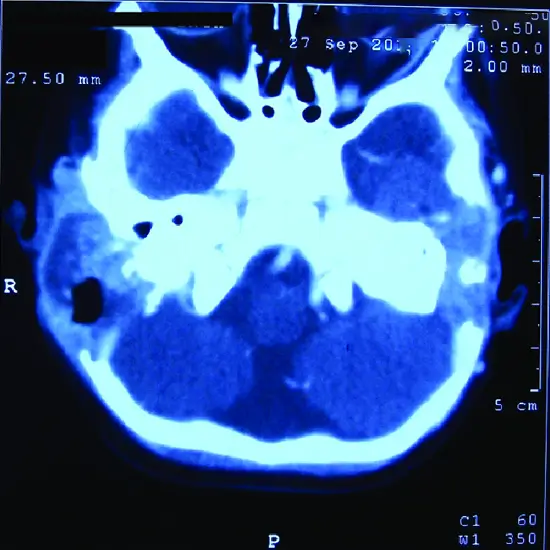

CECT Temporal Bone Axial View (Contrast-enhanced computed tomography of temporal bone axial view). It is used to get the detailed structure of the lower part of the skull to find out the abnormalities in the lower part of the skull and its surrounding tissues at the axial view.

CECT Temporal Bone Axial View is recommended for patients with a severe ear infection, disease or disorders of the middle and inner ear and also hearing loss problems.